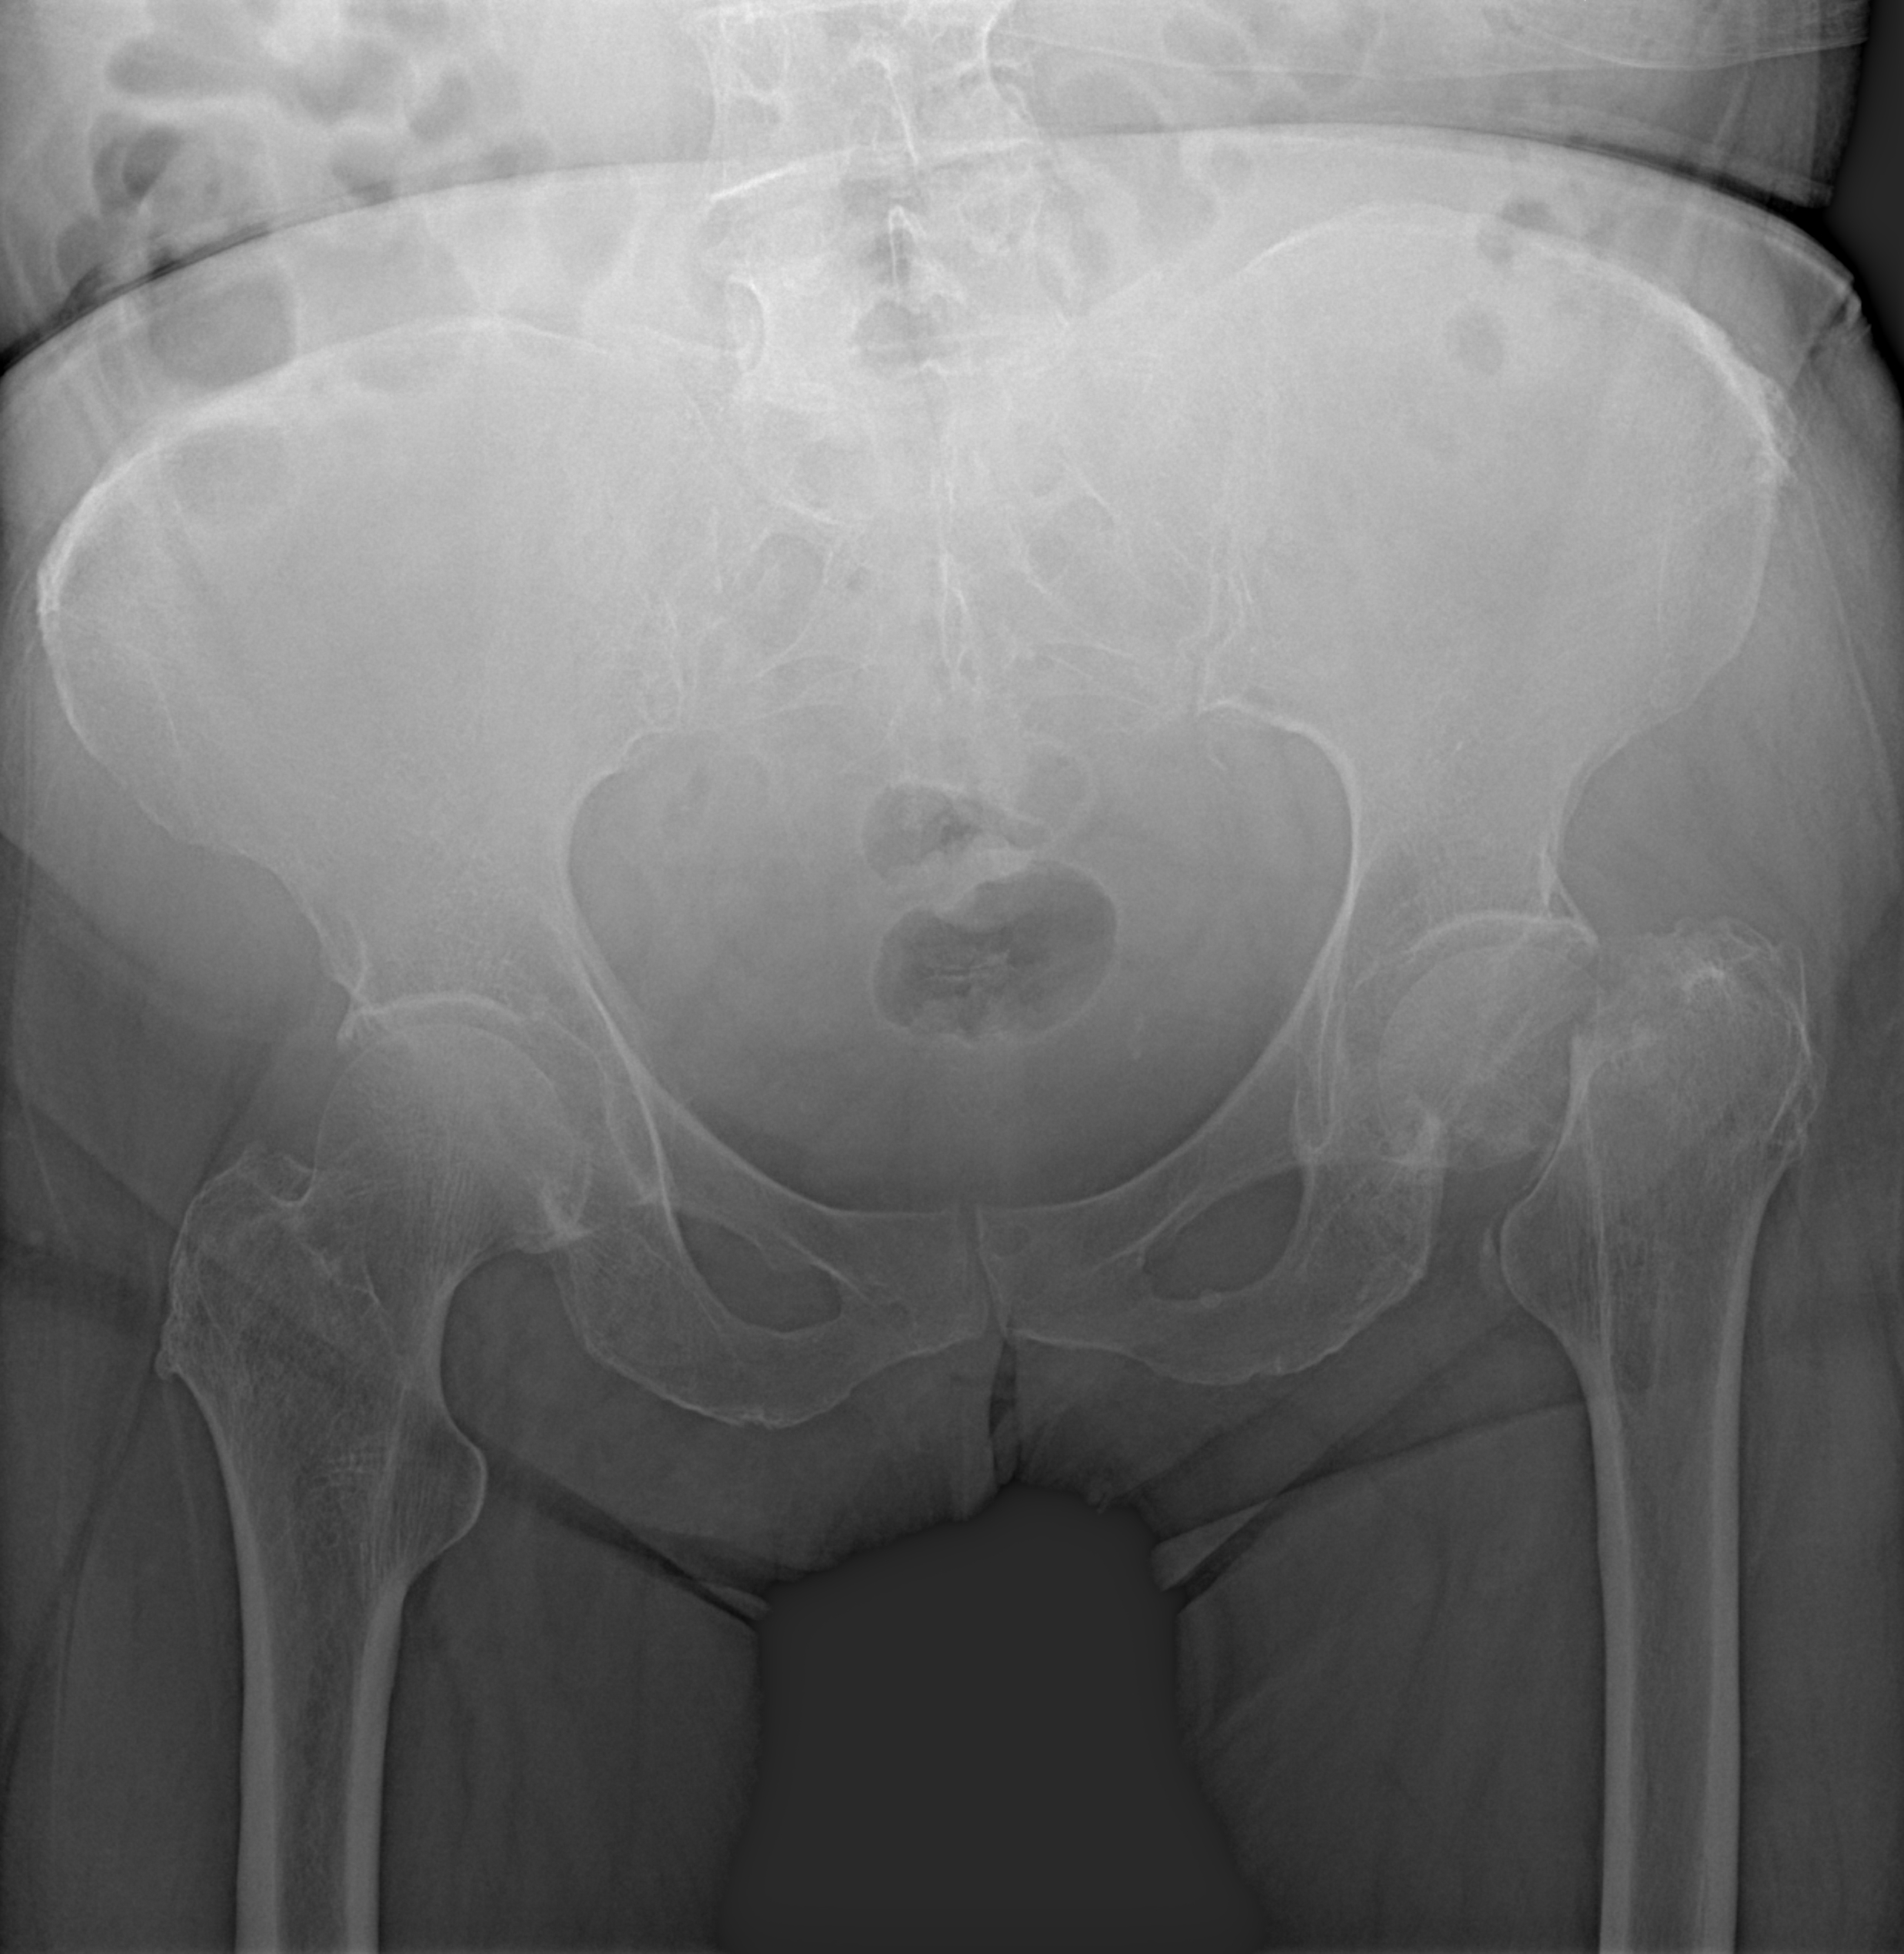

Перелом шейки левой бедренной кости